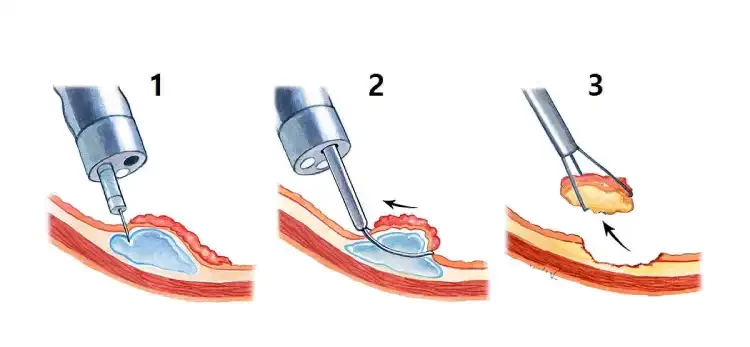

جراحی آندوسکوپی شامل تکنیکهایی مانند برداشتن مخاط آندوسکوپی یا تشریح زیرمخاطی است که اغلب برای پولیپهای بزرگتر از ۱٫۵ سانتیمتر انجام میشود. در تصویر زیر میتوانید آندوسکوپی و برداشتن پولیپ بزرگتر از ۱٫۵ سانتیمتر را ببینید.